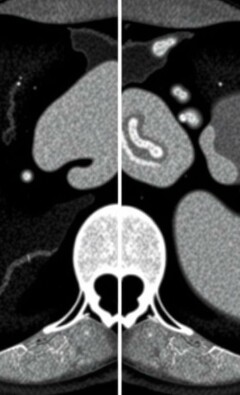

Diferencia entre apendicitis y diverticulitis: cómo reconocer, diagnosticar y tratar dos causas comunes de dolor abdominal